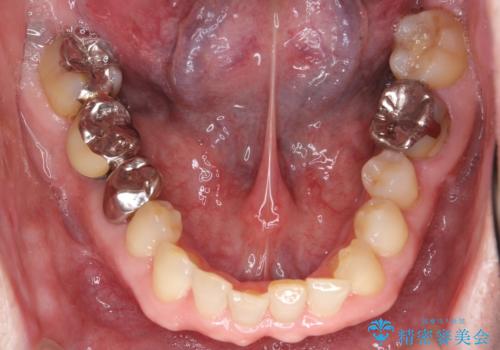

矯正治療後、右下のインレーブリッジおよび左下の銀歯のやりかえを行なっています。

下の前歯はIPR(エナメル質を薄く削り歯を小さくする処置)を行なっています。